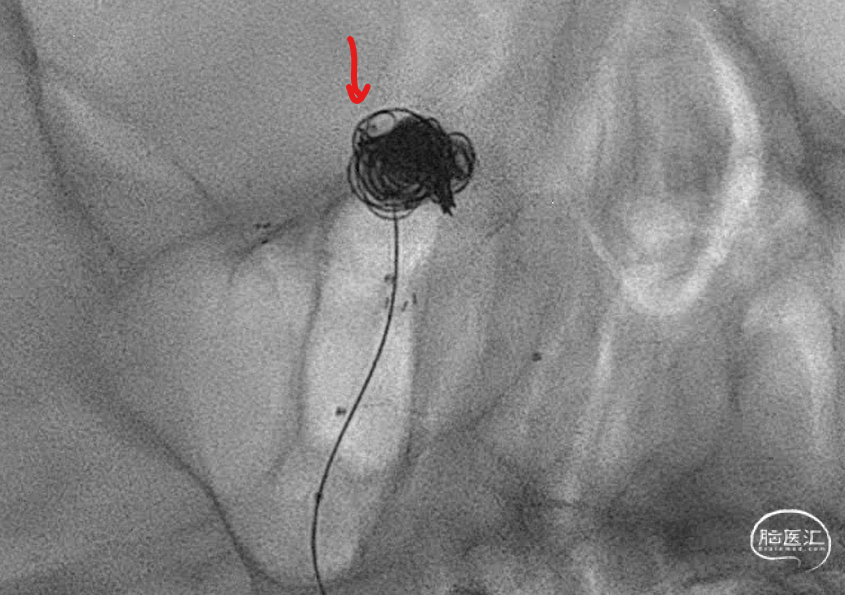

动脉瘤右侧是没事了,但是左侧好像失策了,可以看到左侧部分有一部分圈,但是还是不太致密,但是由于弹簧圈微导管由于在填弹簧圈时,不断减张力,因此已经离开了原来计划的位置。千算万算,好像还是忽略了这一点。

造影显示,左侧大脑后动脉起始似乎还是受到圈的小小影响,最终决定还是把支架放上。

支架释放完毕,感觉还是不太死心,于是调整了微导管几次,由于弹簧圈和支架的阻挡,还是调不进去,如果继续尝试,可能有增加支架内形成血栓的概率和导管可能戳破动脉瘤的风险。于是绝定再造个影看看。